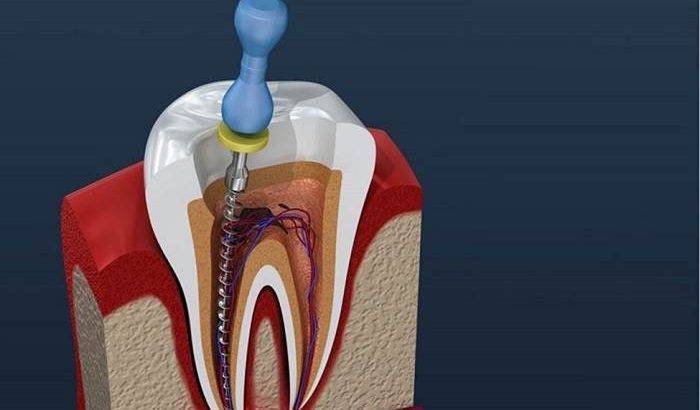

درمان ریشه چگونه انجام میشود؟

متخصصان دندانپزشکی ابتدا ناحیه را بیحس کرده و سپس در داخل دندان سوراخ ایجاد میکنند. دندانپزشک با استفاده از ابزارهای کوچک، پالپ را از محفظه و عصبهای ریشه خارج میکند. ریشهها تمیز شده و شکل داده میشوند تا فضای لازم برای پر کردن ایجاد شود. سپس ریشه با مادهای مانند لاستیک به نام گوتاپرکا پر شده و با یک چسب از بالا بسته میشود. متخصصان برای محافظت از داخل دندان در هنگام بهبودی، مواد پر کننده موقت قرار میدهند.

پس از چند روز ممکن است مواد پر کننده موقت برداشته شده و یک تاج برای ترمیم دندان قرار داده شود.

روش درمان مجدد عصبكشی

در طی درمان مجدد، دندان آسیب دیده دوباره باز میشود تا پزشک به عصب ریشه دسترسی پیدا کند. ممکن است پزشک برای رسیدن به ریشه دندان، به جدا کردن تاجها، ستونها و سایر مواد ترمیمی نیاز داشته باشد. مواد پر کننده اولیه برداشته شده و عصبها کاملاً تمیز میشوند. با استفاده از ذرهبین و نور، منطقه به دقت مورد بررسی قرار میگیرد تا عصبهای اضافی احتمالی یا مناطق غیرمعمول شناسایی شوند.

بعد از تمیز شدن عصبها، دندان دوباره با گوتاپرکا پر میشود و کانالها مهر و موم میشوند. مواد موقت در دندان قرار میگیرد. این روش تحت بیحسی موضعی انجام میشود که منطقه آسیب دیده را بیحس میکند و هر گونه درد و ناراحتی را تسکین میدهد. بیهوشی نیز به بیماران برای آرامش بیشتر کمک میکند.